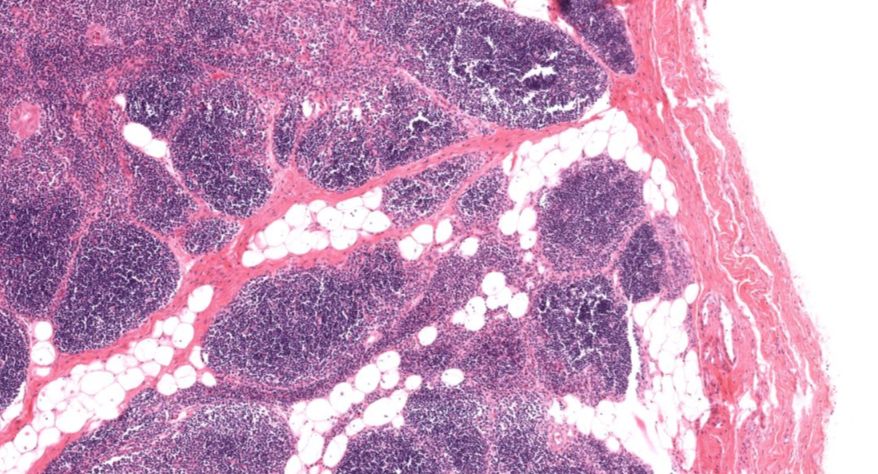

低倍镜:胸腺表面包有薄层结缔组织构成的被膜,结缔组织深入实质,将胸腺分成许多不完整的小叶。每个小叶分为周围的皮质和中央的髓质两部分。皮质中胸腺细胞排列密集,故染色深;髓质中胸腺细胞较少,胸腺上皮细胞多,故染色浅,其中可见染成红色的圆形小体-胸腺小体。高倍镜:胸腺小体大小不等,由几层至十几层扁平的胸腺上皮细胞呈同心圆状排列而成,其外周的细胞较幼稚,细胞核明显;小体中央部分的上皮细胞已退化,细胞核消失,胞质呈均质状,染成红色。

1.成人胸腺全景图

2.被膜

3.皮质

4.髓质